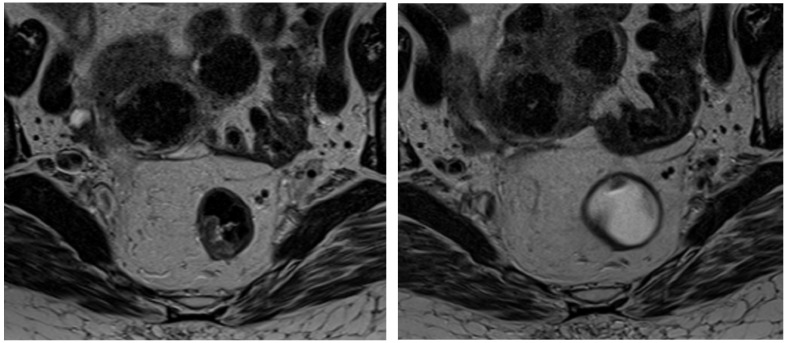

Methods: We conducted a retrospective analysis of adult patients with LARC who underwent pre- and post-nCRT MRI scans. Patients were classified as good responders (Group 0) or poor responders (Group 1) based on MRI findings, including tumor volume reduction, signal intensity changes on T2-weighted and diffusion-weighted imaging (DWI), and alterations in the circumferential resection margin (CRM) and extramural vascular invasion (EMVI) status. Classification criteria were based on the established literature to ensure consistency. Key clinical and imaging parameters, such as age, TNM stage, CRM involvement, and EMVI presence, were recorded. A radiomic model was developed using the LASSO algorithm for feature selection and regularization from 107 extracted radiomic features.

Results: We included 44 patients (26 males and 18 females) who, following nCRT, were categorized into Group 0 (28 patients) and Group 1 (16 patients). The pre-treatment MRI analysis identified significant features (out of 107) for each sequence based on the Mann-Whitney test and t-test. The LASSO algorithm selected three features (shape_Sphericity, shape_Maximum2DDiameterSlice, and glcm_Imc2) for the construction of the radiomic logistic regression model, and ROC curves were subsequently generated for each model (AUC: 0.76).

Conclusions: We developed an MRI-based radiomic model capable of differentiating and predicting between two groups of rectal cancer patients: responders and non-responders to neoadjuvant chemoradiotherapy (nCRT). This model has the potential to identify, at an early stage, lesions with a high likelihood of requiring surgery and those that could potentially be managed with medical treatment alone.